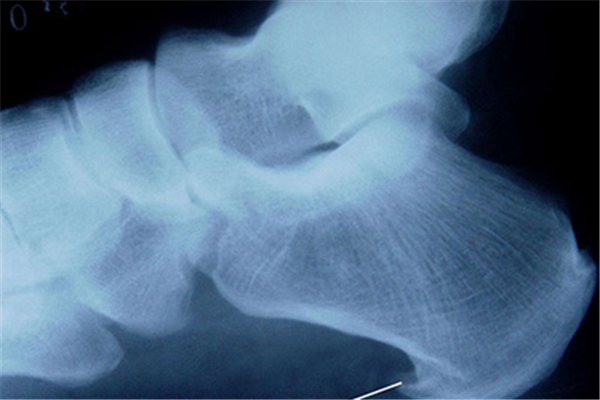

骨質(zhì)增生雖說先開始的時候不會有什么癥狀,但是在后面的時候就會有疼痛的現(xiàn)象,這骨質(zhì)增生是因為缺什么營養(yǎng)所引起的嗎?骨質(zhì)增生是缺鈣嗎?

骨質(zhì)增生并不是因為缺鈣所引起的,骨質(zhì)疏松卻和鈣有一定的關系。骨質(zhì)增生主要是由于周圍肌筋膜軟組織損傷而導致,由于基金膜損傷或者鈣化而導致局部牽引,長時間對骨膜產(chǎn)生牽引而導致骨質(zhì)增生或者是骨刺。

骨質(zhì)增生是一種影像學的表現(xiàn)出,是骨關節(jié)退變致使,通常骨關節(jié)退變后局部穩(wěn)定性上升,反反復復的異常刺激致使局部自身的修補反映,再次出現(xiàn)骨質(zhì)增生,常再次發(fā)生于四肢的關節(jié)部位,和脊柱部位,病發(fā)早期可無明顯癥狀,當炎癥明顯時有疼痛不適癥狀,口服非甾體抗炎藥救治,可以紓解疼痛,壓制纖維化的擴張。需要強調(diào)的是注意多吃一些富含鈣質(zhì)和蛋白質(zhì)的食物,能夠促進骨頭的生長和愈合。

缺鈣和骨質(zhì)增生并沒有明顯的相關性骨質(zhì)增生的發(fā)生,主要就是由于運動量過度產(chǎn)生的,這種情況下就容易導致韌帶反復受到刺激,局部出血,最后形成了骨質(zhì)增生。隨著年齡的增長,身體鈣流失就會逐漸增加,這種情況就會導致缺鈣,需要積極的進行補充鈣質(zhì)。